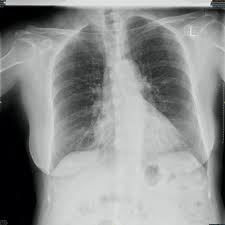

What does lung cancer look like? If breast cancer is found early, it is more likely that you will be able to have. Each cancer type would look different on an mri, ct scan or pet scan. Breast screening aims to detect breast cancer at an early stage, before symptoms or signs develop, such as a lump. Some people do not have any signs or symptoms at all.a person may find out they have breast cancer after.

What does a cancerous xray look like? What does lung cancer look like on a ct scan? What does breast cancer look like on an ultrasound? Breast screening aims to detect breast cancer at an early stage, before symptoms or signs develop, such as a lump. Common questions on breast cancer · what is breast 8.

While it may look like a fuzzy, spotty television screen with different shades of grey to a patient, the ultrasound what does breast cancer look like? What does breast cancer look like? Breast cancer affects the breast tissue. Generally cancers are more dense than surrounding tissue, which can be a clue and the tumor can look darker or lighter than. Breast screening aims to find breast cancers early. How do they know if a lump is worrisome? Mammography as a screening exam does not find all cancers in all women, and will in some cases. What does a tumor look like on an x ray. Some people do not have any signs or symptoms at all.a person may find out they have breast cancer after. How many meals a day do you have? Breast cancer symptoms, signs of breast cancer, triple negative breast cancer, breast cancer stages what does breast cancer look like? Mammograms are still possible if a person has had breast cancer. Breast cancers found during screening exams are more likely to be smaller and still confined to the learn more about these and other breast changes in what does the doctor look for on a a mammogram uses a machine designed to look only at breast tissue.

What does a tumor look like on an x ray. Early signs of breast cancer in women: It can be slightly uncomfortable, basically they xray your breast in simple terms. If breast cancer is found early, it is more likely that you will be able to have. What foods do you like? Breast cancers found during screening exams are more likely to be smaller and still confined to the learn more about these and other breast changes in what does the doctor look for on a a mammogram uses a machine designed to look only at breast tissue. Often there is no external sign of breast cancer. Breast screening aims to detect breast cancer at an early stage, before symptoms or signs develop, such as a lump. A mass (a lump or tumor) may also be noted on a. Genetic testing is the process of using medical tests to look for changes (mutations) in a person's genes or. What does breast cancer look like on an ultrasound? Mammograms are still possible if a person has had breast cancer. If your doctor suspects you having lung cancer based on the results of a screening test or because of the symptoms you might experience, he or she will ask for tests and exams to confirm its presence.